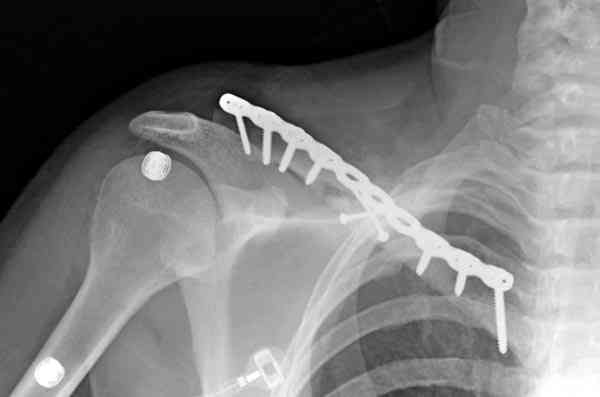

Недавно разбирали случай ложного сустава.

45 летная женщина после автоаварии, алкоголь 163 и 20 летним стажем курения.

Консервативное лечение, через 8 мес. операция Rockwood pin с костной пластикой в нашем городе другим врачом. После 8 недели падение, гвоздь удален оперирующим хирургом, больная направлена к нам. Фиксация реконструктивной пластиной с трикортикальным графтом, добавлен BMP-2. Для стабилизации фиксацию провели через акромион.

Вот уже два месяца больная также продолжает жаловаться на боли, буквально на днях удалили акромиальную часть пластины с специальной пилой с алмазным покрытием для медицинского металла. До сих пор судьба ложного сустава неизвестна....

Второй случай тоже недавно оперирован по поводу

ложного сустава, в марте травма, через 4.5 половиной

операция..